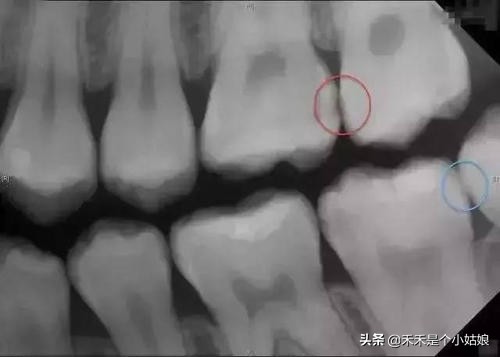

结果出来了,女儿有三颗牙齿需要补,一颗需要根管治疗,于是我跟医生简单交流了下治疗过程,带着女儿看了下她“牙齿的照片”。这时的她已经开始逐渐放松警惕,医生建议我今天先给她补一颗蛀牙最轻的牙齿,让女儿感受下治疗的过程,不要一次性让她接受太多,导致再次排斥看牙医。在治疗的时候治疗室有电视*放播**动画,护士也给了她一些关于牙齿的玩具,还有在做每一个动作之前都会提前给她讲述下感受,并且让她用手提前感受下治疗器械和器械对她身体带来的感觉,就这样女儿顺利的补了一颗牙,治疗完医生还鼓励性的奖励了几个小贴纸,最后女儿开心的结束了治疗过程,当然走的时候我也兑现了之前的承诺给她买了玩具。完美的结束了第二趟看牙医之旅。